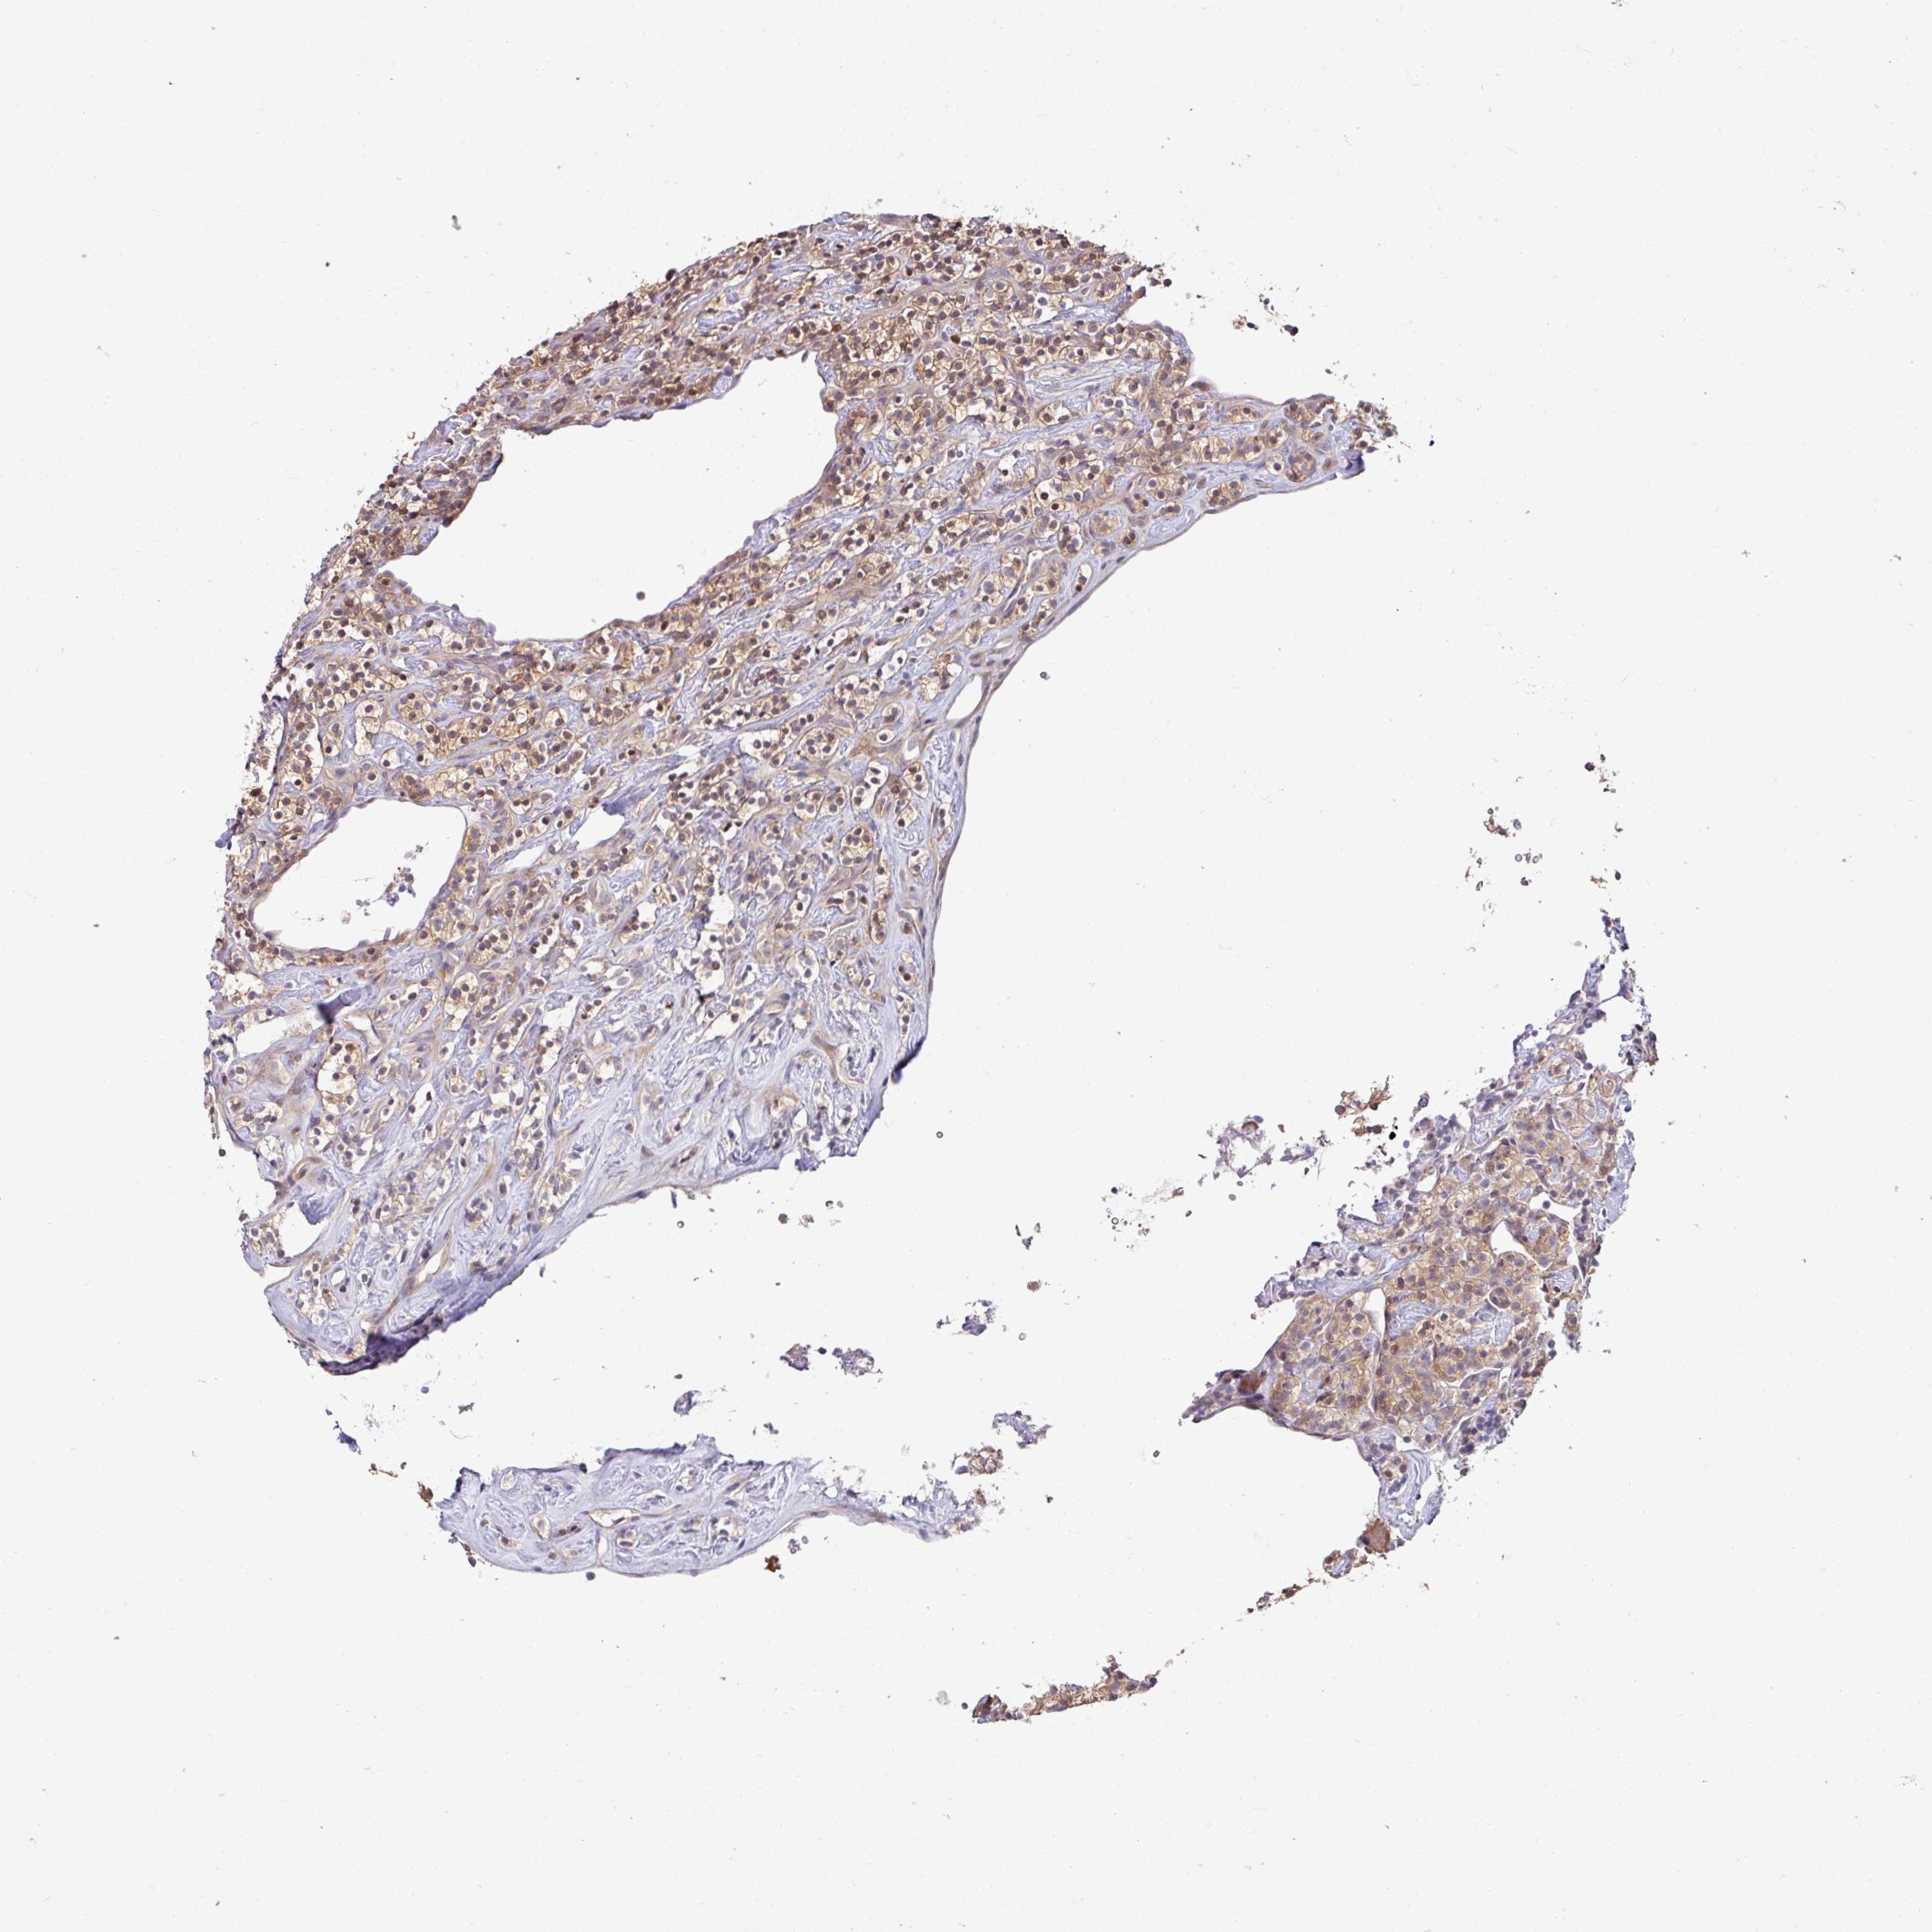

KIDNEY RENAL CLEAR CELL CARCINOMA (VALIDATION) - Interactive survival scatter ploti

The Survival Scatter plot shows the clinical status (i.e. dead or alive) for all individuals in the patient cohort, based on the same data that underlies the corresponding Kaplan-Meier plots. Patients that are alive at last time for follow-up are shown in blue and patients who have died during the study are shown in red.

The x-axis shows the expression levels (FPKM) of the investigated gene in the tumor tissue at the time of diagnosis. The y-axis shows the follow-up time after diagnosis (years). Both axes are complimented with kernel density curves demonstrating the data density over the axes. The top density plot shows the expression levels (FPKM) distribution among dead (red) and alive patients (blue). The right density plot shows the data density of the survived years of dead patients with high and low expression levels respectively, stratified using the cutoff indicated by the vertical dashed line through the Survival Scatter plot. This cutoff is automatically defined based on the FPKM cutoff that minimizes the p-score. The cutoff can be changed by dragging the vertical line or by entering a cutoff value in the square labeled "Current cut-off".

Under the Survival Scatter plot the p-score landscape (black curve; left axis) is shown together with dead median separation (red curve; right axis). Dead median separation is the difference in median mRNA expression between patients who have died with high and low expression, respectively. It is calculated as follows: median FPKM expression of dead patients with high expression - median FPKM expression of dead patients with low expression. This is intended to aid the user in visually exploring custom cutoffs and the associated p-scores and dead median separation.

Individual patient data is displayed and can be filtered by clicking on one or more of the category buttons on the top of the page. Categories describing expression level and patient information include: high, low, alive, dead, female, male and tumor stages. The scale of the x-axis can be toggled between linear and log-scale by clicking on the "x log" button. Mouse-over function shows TCGA ID, patient information and mRNA expression (FPKM) for each patient.

& Survival analysisi

Kaplan-Meier plots summarize results from analysis of correlation between mRNA expression level and patient survival. Patients were divided based on level of expression into one of the two groups "low" (under cut off) or "high" (over cut off). X-axis shows time for survival (years) and y-axis shows the probability of survival, where 1.0 corresponds to 100 percent.

SLAMF6 is not prognostic in Kidney Renal Clear Cell Carcinoma (validation)

Best expression cut offi

Based on the FPKM value of each gene, patients were classified into two groups and association between prognosis (survival) and gene expression (FPKM) was examined. The best expression cut-off refers the FPKM value that yields maximal difference with regard to survival between the two groups at the lowest log-rank P-value. Best expression cut-off was selected based on survival analysis .

When clicking on this number, the vertical dashed line indicating cut-off, the interactive survival plot, and the Kaplan-Meier curve will be adjusted to show results based on the best expression cut-off.

: 2.44

P scorei

Log-rank P value for Kaplan-Meier plot showing results from analysis of correlation between mRNA expression level and patient survival.

N/A

TCGA RNA samplesi

RNA-seq data is reported as average FPKM (number Fragments Per Kilobase of exon per Million reads), generated by the The Cancer Genome Atlas (TCGA) .

Normal distribution across the dataset is visualized with box plots, shown as median and 25th and 75th percentiles. Points are displayed as outliers if they are above or below 1.5 times the interquartile range. FPKM values of the individual samples are presented next to the box plot.

Average pTPM 6.5

Number of samples 100